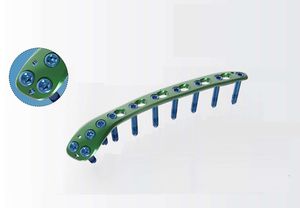

... ¢3.5/¢4.0后壁髋臼重建板 255.1141632.15 - ¢3.5/¢4.0后壁髋臼-H板,16H L 255.2141632.15 - ¢3.5/¢4.0后壁髋臼-H板,16H R 255.1140932.15 - ¢3.5/¢4.0后壁髋臼重建板,9H L 255.2140932.15 - ¢3.5/¢4.0后壁骨盆重建板,9H R 255.1141132.15 - ¢3.5/¢4.0后壁骨盆重建板,11H L 255.2141132.15 - ¢3.5/¢4.0后壁髋臼重建板,11H ...

Health-Joy Medical

... 255.1141632.15 - ¢3.5/¢4.0后髋臼-H 夹板 16H,L 255.2141632.15 - ¢3.5/¢4.0后髋臼前板 16H,R ...

Health-Joy Medical

... 255.0150232.15 - ¢3.5/¢4.0髋臼弹簧钩板,短 255.0150332.15 - ¢3.5/¢4.0髋臼弹簧钩板,长形 ...

Health-Joy Medical